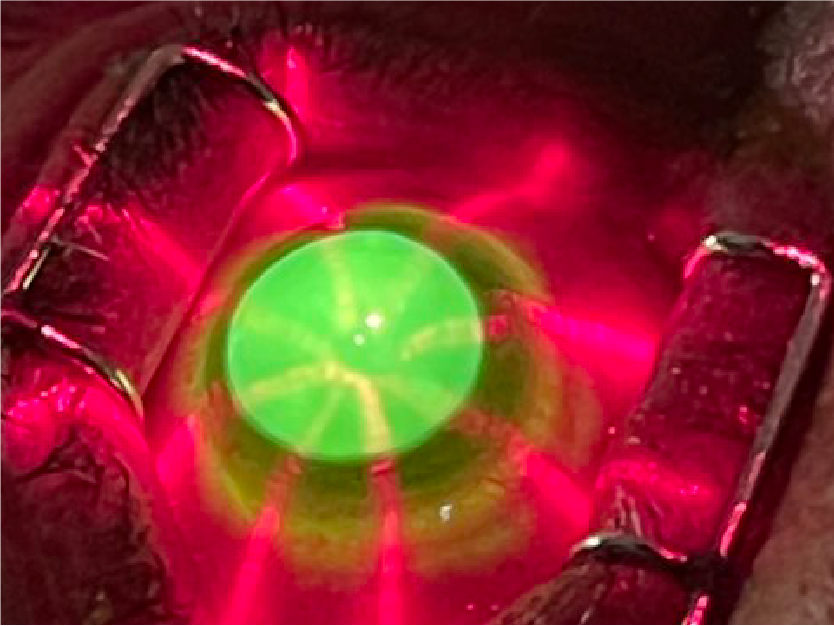

Cataract Surgery

Cataracts are the most common reason for vision loss in the U.S., and Parker Cornea provides specialized procedures to combat the disease, including Toric lenses and EDOF / Multifocal lenses.